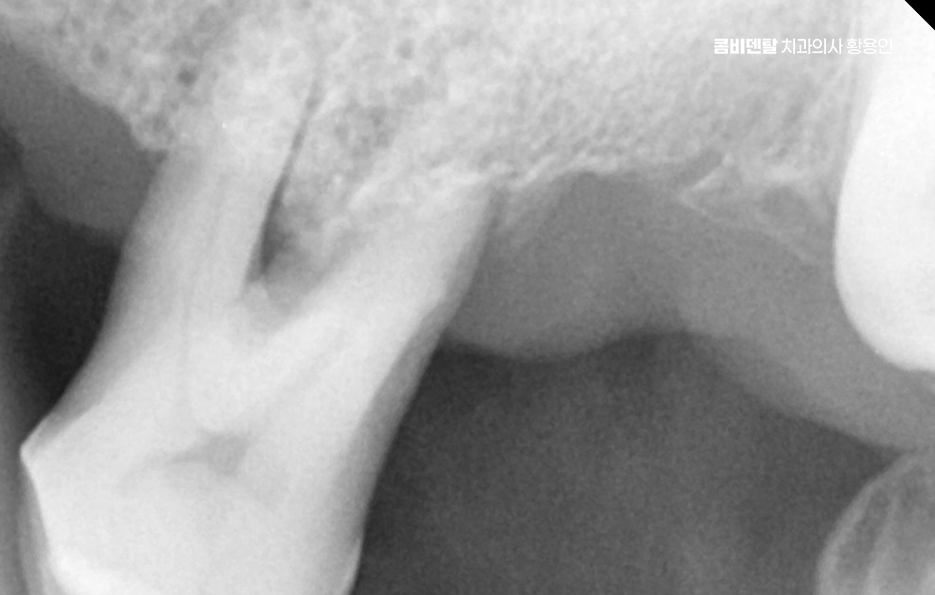

보통 윗니 전체 임플란트를 계획할 때 먼저 해야 하는 건 CT 촬영을 통한 잇몸 뼈 상태 진단으로 윗니는 아래보다 뼈가 더 얇고, 특히 어금니 쪽에는 상악동이라는 빈 공간이 있기 때문에, 임플란트를 심을 수 있는 잇몸 뼈의 양이 부족한 경우가 많다보니 이런 경우에는 단순히 임플란트를 심을 수 없기 때문에 상악동 거상술이라는 수술이 필요하게 되는 경우도 있는데요

이 수술은 상악동 점막을 들어 올리고 그 아래에 뼈이식 재료를 넣어서 임플란트가 들어갈 수 있는 충분한 공간을 만들어주는 방식이며 그 외에도 잇몸 뼈 상태나 전신 건강, 흡연 여부 같은 조건에 따라 구체적인 치료 방법이 달라지기 때문에 이처럼 윗니 전체 임플란트의 경우 기본적으로 임플란트를 지지할 수 있는 잇몸 뼈가 충분한지 정확한 진단이 치료의 시작점이 되고 있어요